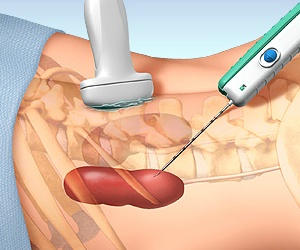

BÖBREKTEN PARÇA ALMA (BİYOPSİ)

Böbrek hastalığının nedenini anlamak için böbrekten parça almak gerekebilir. Parça almak deyince hastanın aklına genellikle kanser gelir. Nefroloji pratiğinde ise parça almanın amacı çoğu kez kanser değildir. Günümüzde ultrasonografi yardımı ile böbrekten parça almak oldukça kolay bir işlemdir ve riskleri çok azalmıştır. Özel durumlarda böbrek biyopsisi açık veya laparoskopik yapılabilir.

Böbrek biyopsisinin başlıca riskleri kanama ve ağrıdır ancak gerekli ön hazırlıktan ve işlem sonrası yakın takiple ultrasonografi yardımı ile biyopsi yapılması bu riskleri minimuma indirmiştir. Biyopsinin riskleri olduğu doğrudur ama biyopsi yapmamanın da riskleri vardır. Biyopsi zaten hastaya yararlı olabilecek bir tedavi seçeneği olduğu zaman gündeme gelir.